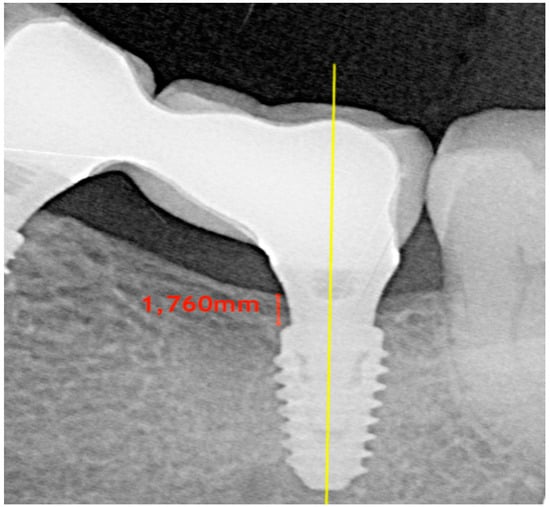

2.4. Radiographic Measurements

| Insertion Depth | N° Of Implants | Mean Depth At T0 | Mean Depth At T4 |

|---|---|---|---|

| >1.5 mm | 20 | 2.01 ± 0.48 mm | 0.94 ± 0.76 mm |

| <1.5 mm | 63 | 1.00 ± 0.34 mm | 0.31 ± 0.42 mm |